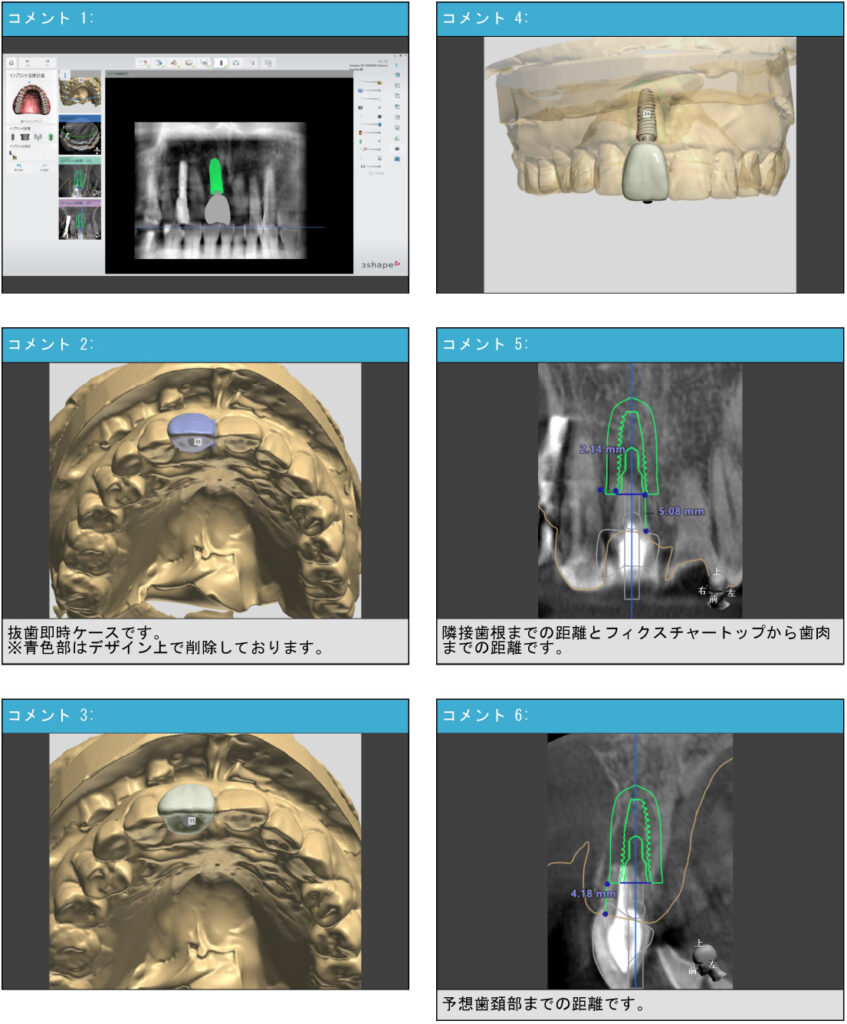

サージカルガイドとは、インプラントを埋め込むためのオーダーメイドの「手術用テンプレート」です。事前に撮影したCTデータを用いてコンピューター上で緻密なシミュレーションを行い、インプラントを埋入する最適な位置、深さ、角度を正確に設定して作製します。

コンピュータ上で、骨の量や形、神経・血管の位置を正確に把握し、インプラントがどのように入るかをシミュレーションします。

さらに、最終的な被せ物(上部構造)のことも考慮し、他の歯との噛み合わせや審美性のバランスをシミュレーションすることで、機能的にも見た目にも美しい仕上がりを目指します。

- 精密検査: 3DでのCT撮影を行い、顎の骨や神経、血管の位置などを詳細に確認します。

- シミュレーション: 取得したデータを基に、コンピューター上でインプラントの最適な埋入位置をシミュレーションします。

- ガイド作製: シミュレーション結果に基づいて、正確な位置にインプラントを埋入するためのサージカルガイドを作製します。

- 手術: ガイドを装着した状態で手術を行うため、歯茎の切開を最小限に抑え、計画通りにインプラントを埋入します。